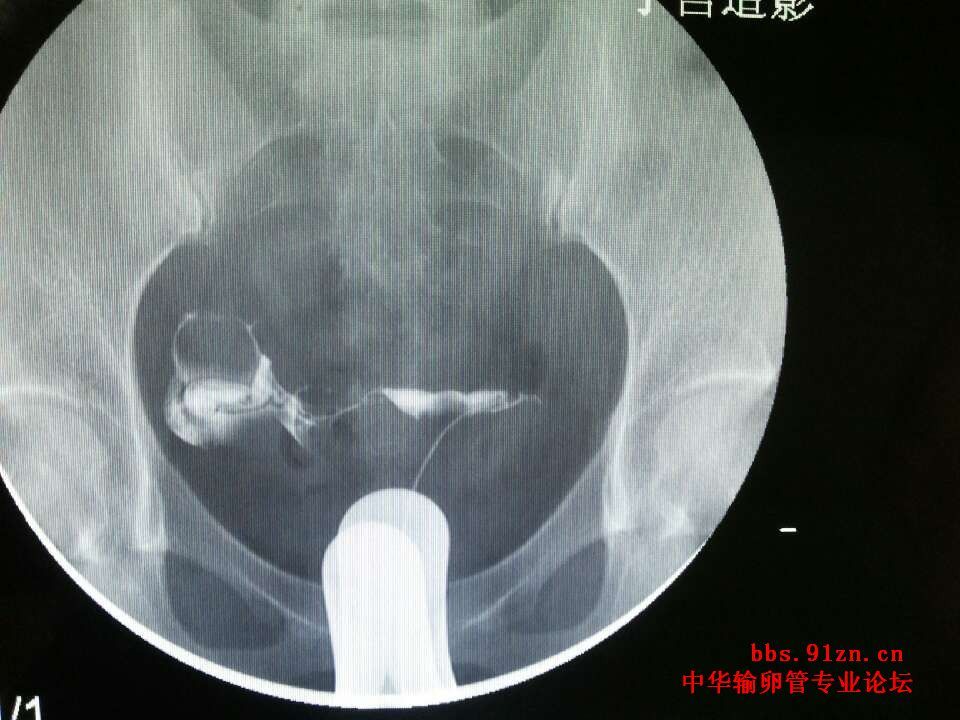

请大夫看看输卵管造影片

年龄:(29 )岁 ;近期查出多囊卵巢综合症,左右各11.12个卵泡,小于6mm 已经试孕( 半)年; 平时月经周期不准,月经持续3 天; 既往怀孕(1   )次,流产( 1)次药流,最近一次流产距今(5  )年; 男方的精液检查结果( a+b=40%,a18%);

您的片子上没有标左右,您有一侧没有显影,显示阻塞,或者是切除过一侧输卵管,另一侧虽然通畅,但是略有些粘连,但是您不怀孕的主要原因是多囊的问题,卵巢不排卵肯定怀不上孕,您这种该情况可以手术治疗,一是治疗多囊,二是探查另一侧不通的,通的那侧粘连可以分解开,没有其他问题术后第二个月就有自然受孕的机会。